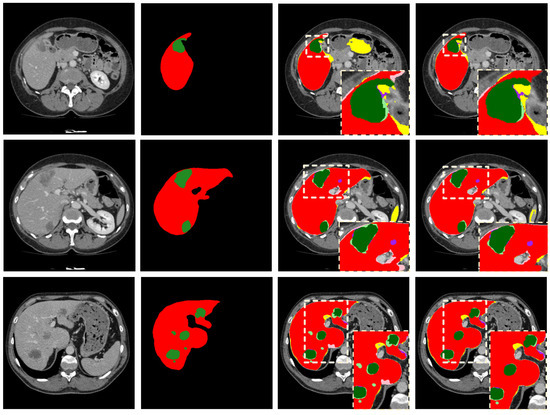

- A cascading 2.5D FCNs based on the residual network is proposed, which can effectively segment the liver and tumor in CT images and can reduce VRAM cost;